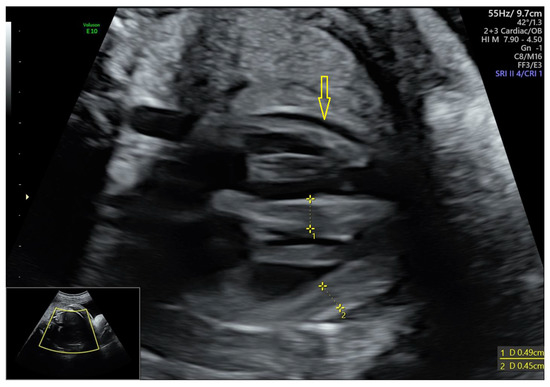

3.1.2. Data of the Instrumental Methods of Examination